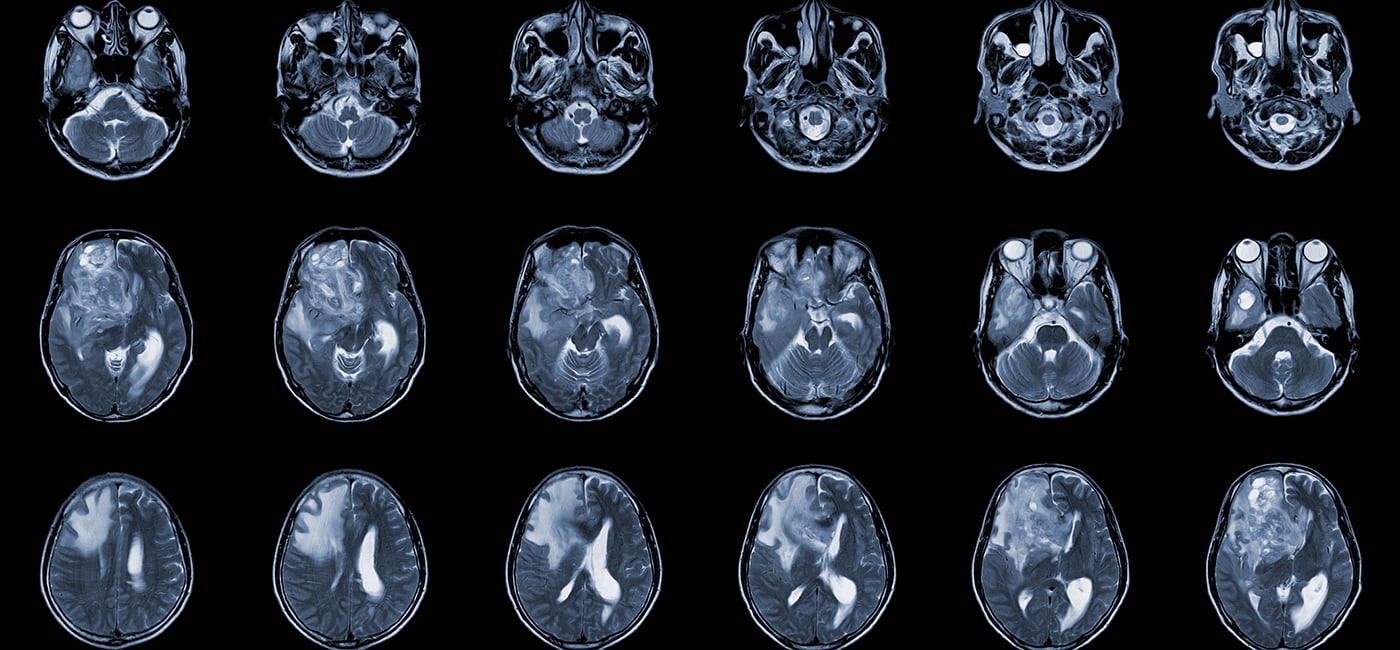

With a five-year survival rate of less than 10%, glioblastoma is one of the most aggressive forms of brain cancer. The disease gained national attention after claiming the lives of Edward Kennedy, John McCain and Beau Biden. It has no cure and has seen minimal progress in drug treatment over the past two decades.

But two clinical trials published this month in the New England Journal of Medicine and Nature Medicine offer a glimmer of hope. Both trials looked at the effects of chimeric antigen receptor T-cell therapy, or CAR T therapy, in patients whose glioblastoma returned following their initial treatment.

While the trials were very small, both showed that CAR T was safe and shrank tumors.